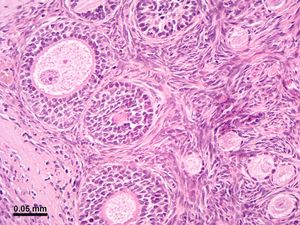

난소는 백색의 섬유성 낭에 덮여 있으며, 난소의 내부는 안쪽으로는 섬유결합조직과 혈관인 수질(속질, medulla), 난자가 자라는 곳인 바깥쪽의 피질(겉질, cortex)로 구분된다.[68] 피막은 치밀 결합조직으로 이루어져 있으며, 백막으로 알려져 있다.[4]난소의 표면은 단층 입방 상피에서 원주 상피 모양의 중피 세포로 이루어진 막, 즉 생식 상피로 덮여 있다.[7] 바깥층은 난소 피질이며, 그 사이에는 난포와 기질이 있다. 난포에는 난구, 과립막(그리고 그 안의 과립막 세포), 방사관, 투명대, 그리고 1차 난모세포가 포함된다. 난포막, 난포강과 난포액도 난포에 포함된다. 또한 피질에는 난포에서 유래된 황체가 있다. 가장 안쪽 층은 난소 수질이다.[8] 피질과 수질을 구분하기 어려울 수 있지만, 수질에는 일반적으로 난포가 없다. 난소에는 혈관과 림프관도 있다.[9]

난포 세포는 난소를 덮는 표면 상피에서 유래한 편평 상피세포이다. 이 세포들은 편평 세포에서 입방형으로 변하고 증식하여 중층 상피를 생성하는 과립막 세포로 둘러싸여 있다.

'''난포'''는 난소 안에 다수 존재하는 구상의 세포 덩어리로, 그 안에는 1개의 난자 세포가 포함되어 있으며, 난소의 세포가 그것을 둘러싸고 있는 구조이다. 난포는 배란이 일어날 때의 기능적 단위이다. 난포는 그 발달 단계에 따라 다른 이름으로 불린다.

- '''원시난포''': 난소 안에 항상 무수히 축적되어 있는 휴면 상태의 난포이다. 1개의 난자 세포와 그것을 둘러싸는 1층의 세포층으로 구성된다. 둘러싸고 있는 세포는 '''난포상피세포'''라고 불린다. 난소의 표면 근처에 빽빽하게 나란히 늘어서 있다.

- '''1차 난포''': 휴면에서 깨어난 원시난포는 발달을 시작하는데, 그 처음 며칠 동안의 난포이다. 이 기간 동안, 난자 세포를 둘러싸는 난포상피세포가 세포 분열을 반복하여 그 수를 늘리면, 난자 세포를 둘러싸는 층이 처음에는 1층의 세포였던 것이 2층, 3층으로 늘어난다. 난자 세포 자체의 크기는 변하지 않지만, 난포의 크기는 점차 커진다. 다층화된 난포상피세포의 층을 '''과립층'''이라고도 부른다. 또 이것을 둘러싸는 것처럼, 그 바깥쪽에 난포막 또는 피막이라고 불리는 구조가 나타난다. 난포막은 1~수층의 편평한 세포층이다.

- '''2차 난포''': 1차 난포 이후, 배란에 이르는 최종 발달 단계까지의 난포를 말한다. 난포상피세포가 증식을 반복하고 과립층이 두꺼워지면, 이 안에 난포강이라고 불리는 공동이 나타나기 시작한다. 난포강에는 과립층의 세포에서 히알루론산 등에 풍부한 액체가 분비되어 축적되고, 점차 난자 세포를 난포 내의 끝으로 밀어낼 정도로 넓어진다. 또, 난포의 가장 바깥쪽에 있는 난포막은 2종류의 세포로 구성된 2층으로 나뉘어, 외난포막, 내난포막(외피막, 내피막)이 구별될 수 있게 된다. 최종적으로 배란 직전에는 1개의 난포의 크기는 18~20mm 정도가 되는데, 이 배란 직전의 난포를 '''성숙난포'''('''그라프난포''')라고 부른다.